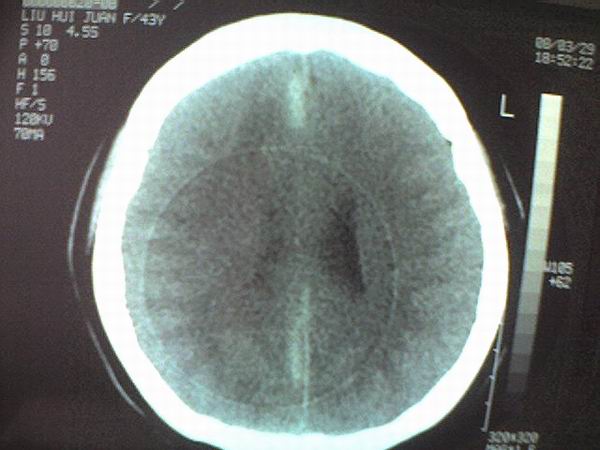

标题: CT12572:女 43岁 头痛恶心呕吐两天请求会诊 [打印本页]

女 43岁 头痛恶心呕吐两天

手机照的,不是太清楚。

右侧大脑镰硬膜下出血

1、右侧大脑镰硬膜下出血2、机器伪影太重,该修修。